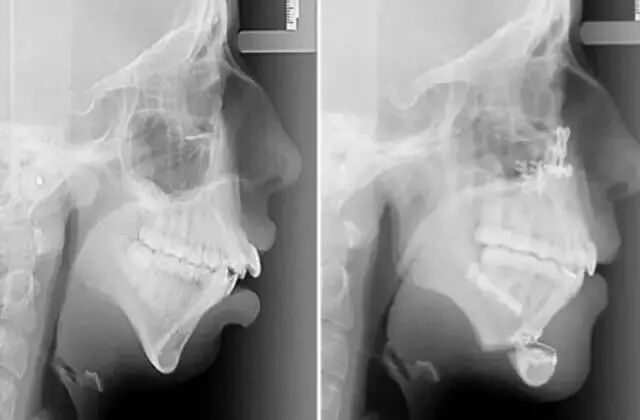

图片来自腾讯国际新闻

腾讯国际新闻对事件的描述是这样的:“16岁时,琼斯接受了第一次下颌手术,她说,那一个月我只能吃流食,非常痛苦,而且我无法正常说话,跟人说话要写在本子上。接下来的一年里,牙医与颌面部修复医生多次会诊,为琼斯进行了下颌修复手术,将她的下颌截掉了一块,植入新的下颌骨。”

从14岁正畸开始,历经6年,在接受了正畸和下巴重建手术后,这位女孩的面容变得靓丽动人,她也终于能够重拾自信。治疗成功后,艾丽•琼斯激动地表示:“这改变了我的一生。”